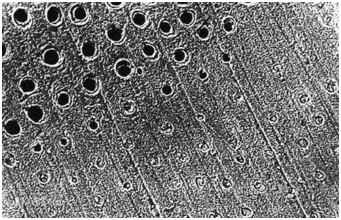

圖中上半部分牙本質(zhì)采用37%磷酸酸蝕15秒徹底沖洗后牙本質(zhì)橫斷面,可見玷污層已經(jīng)被去除(放大倍數(shù)1000)